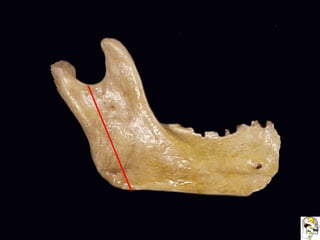

Antilíngula

Obtenido de casos de internet